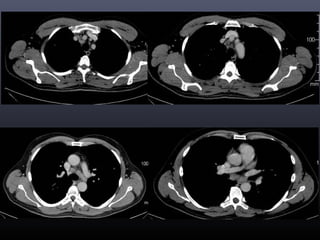

Tc torax 28-06-2011

• CONCLUSION TOMOGRAFICA:

• Nódulo pulmonar cavitado en el segmento 4 izquierdo con

afección de parénquima adyacente, lo cual como primera

posibilidad corresponde a Tuberculosis y diagnostico

diferencial de Coccidiodiomicosis.